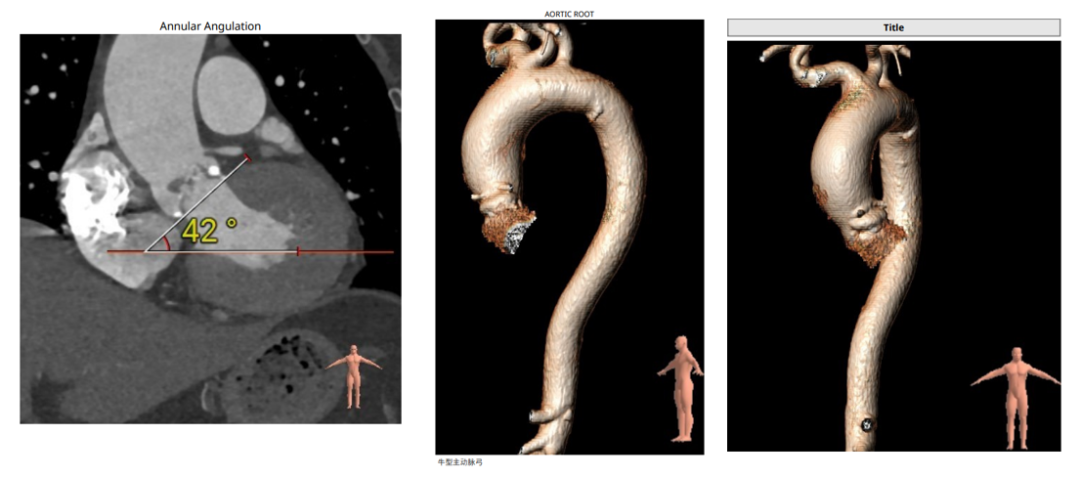

主动脉瓣根部:

CUSP OVERLAP植入视图:

Type0型二叶瓣环上结构:

瓣膜尺寸的选择:预装26,备选29: